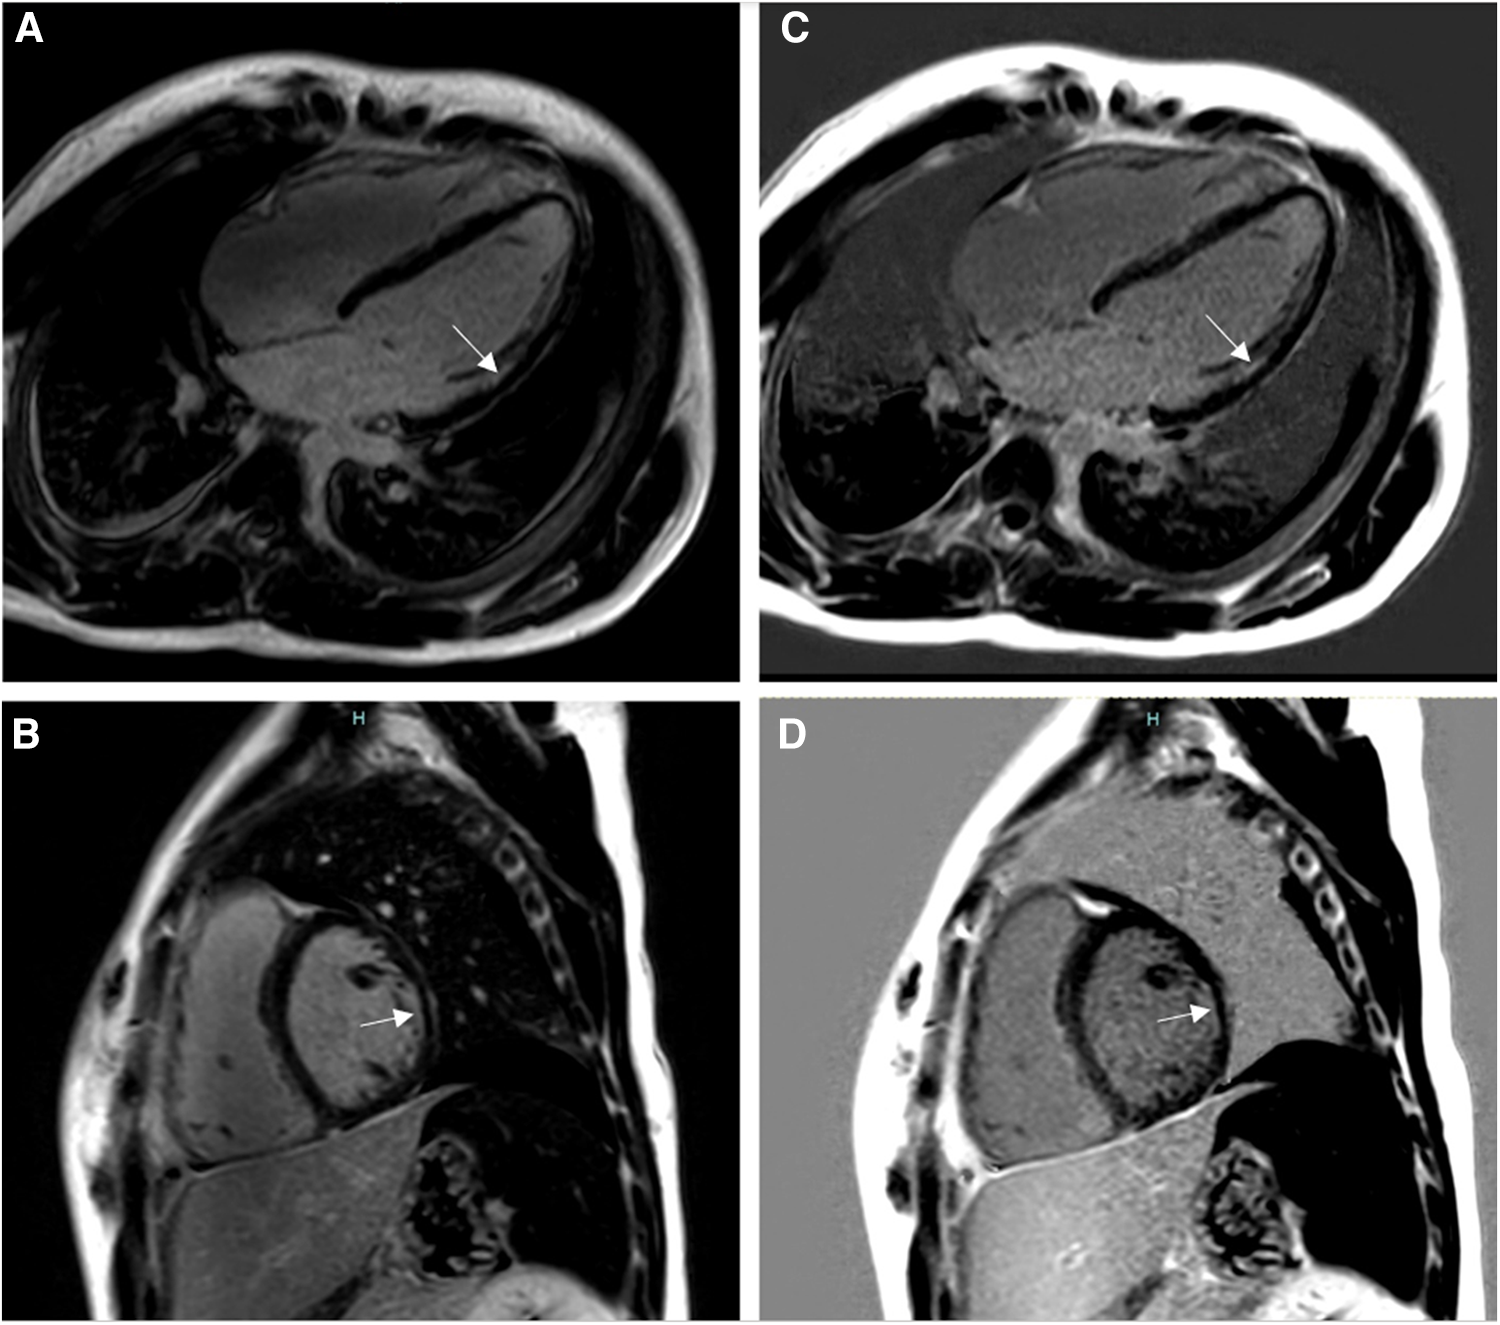

Figure 4

Fourteen-year-old admitted for ventricular fibrillation. (A,B) show conventional BB-LGE sequences; subendocardial scar is somewhat difficult to visualize given its similar signal intensity to the blood pool. (C,D) show gray-blood LGE sequences; the scar is relatively easier to see. Ultimately, utilization of both sequences increased the readers’ confidence in correctly diagnosing it.